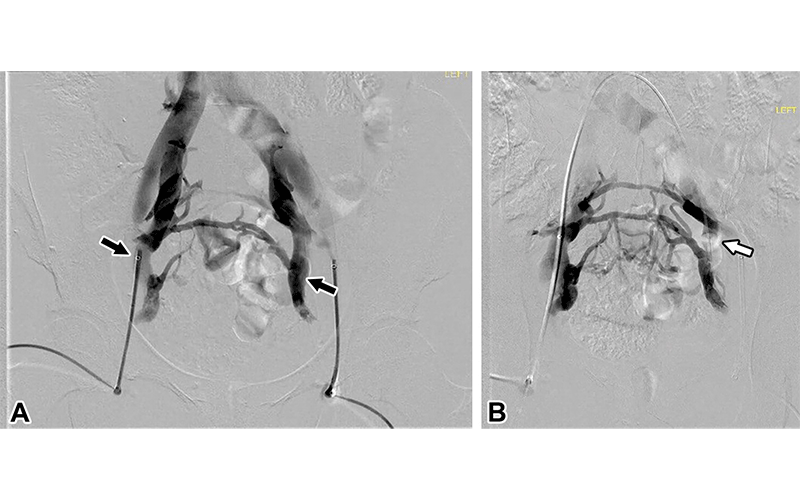

Uterine artery embolization (UAE) is the most studied for treatment of uterine fibroids and is also being researched as an alternative treatment for hysterectomy and myomectomy.

UAE for treatment of symptomatic fibroids consists of selectively catheterizing the uterine artery (UA) with subsequent delivery of permanent particles into the perifibroid plexus vasculature. Due to the permanent effect of the embolization, there is a noticeable reduction of fibroids’ size and associated symptoms. It is a minimally invasive alternative for women wishing to avoid hysterectomy.

Several interventional radiology techniques are available for obstetric patients with conditions associated with high-risk bleeding. UAE can be used for primary and secondary postpartum hemorrhage and in some instances may be performed in place of hysterectomy. UAE is also effective for patients with placenta accreta spectrum for planned cesarean hysterectomy.

Interventional options include the placement of occlusion balloons before surgery, embolization before surgery, and embolization after delivery but before surgery. Endovascular occlusion balloon placement has been shown to significantly reduce blood loss, transfusion requirements, intensive care unit admissions, and overall adverse events. Growing evidence is now demonstrating that UAE following cesarean delivery before hysterectomy decreases the risk associated with uncontrollable post-partum hemorrhage in these patients.